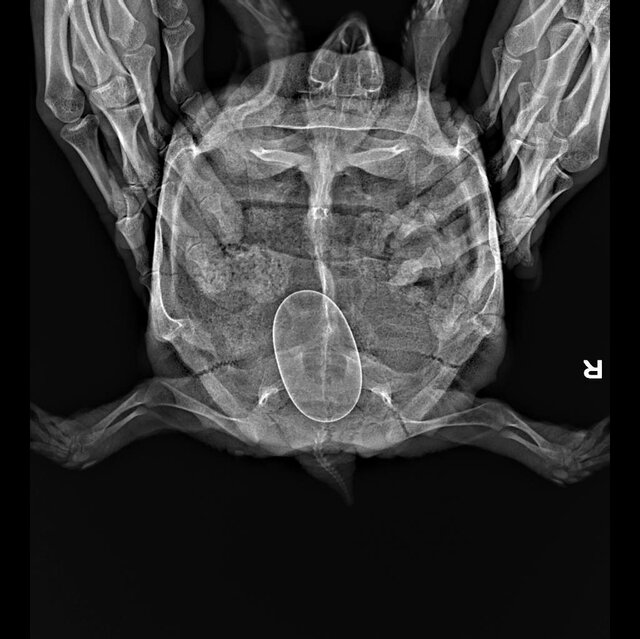

Если кратко, за последние несколько лет мне отдали знакомые люди две черепахи. Я стала за ними ухаживать, любить и растить, купила террариум, лампы, набираю сено на зиму на подстилку, летом гуляют в вольере на улице. В общем оказалось, что они разнополые, когда только появлялась каждая из них я не смогла различить, потому что были похожи. Но когда они стали половозрелые, я подумала может у них что-то получится и это случилось в этом году. На ренгене (30.09.2023) я узнала, что у девочки одно яйцо и она начала проявлять беспокойство, отказывалась от еды и закапывалась в подстилку. В клинике сказали ждать, у них не было такого опыта с беременными сухопутными черепахами. Я начала искать информацию в интернете, смотреть видео и вроде бы всё окей она сама прекрасно справится. Но сегодня 27 октября, я уже с нейросетью искала информацию, очень переживаю и уже готова пойти в ветклинику и последовать совету лопнуть и вытащить яйцо, как это делают попугаям с проблемой откладки. У меня нет в городе больше специалистов в принципе по черепахам. Есть ли тут ветврачи или люди с опытом, что может помочь определить проблему? Или всё нормально и стоит бить тревогу, если она и за ноябрь не отложит яйцо?

Клоака увеличилась за последние пару дней, отверстие будто стало больше и она стала часто тужиться, мне предлагали немного вазелином смазывать, так я заметила, что яйцо ушло глубже, потому что оно было почти у отверстия. Сказали прививки не надо, потому что витамины делали в июле, яйцо очень твердое и кальция нормально в организме. Может у неё яйцо не в правильном положении? Вот прилагаю ренген. Если всё серьезно я поеду в Москву, если вариант, что в ветклинике как попугаю вытащат яйцо - хорошо я так и сделаю. Я купаю раз в неделю в тазике черепаху, оставляю в теплой воде, аппетит хороший и пьет из миски воду сама. Но тужится, и так весь месяц по нарастающей, я боюсь, что это долго

Девочка, среднеазиатская черепаха, больше 10 лет, вес 704гр

врач ответила, что яйцо крупное, но должно быть всё хорошо. Но если будет видно, что яйцо стоит в клоаке и ни туда ни сюда - да, можно как с птицами, вагинальным зеркалом расширить клоаку, асперировать содержимое яйца иглой и пинцетом вытащить скорлупу. Но это должен делать тот, кто понимает что делает.